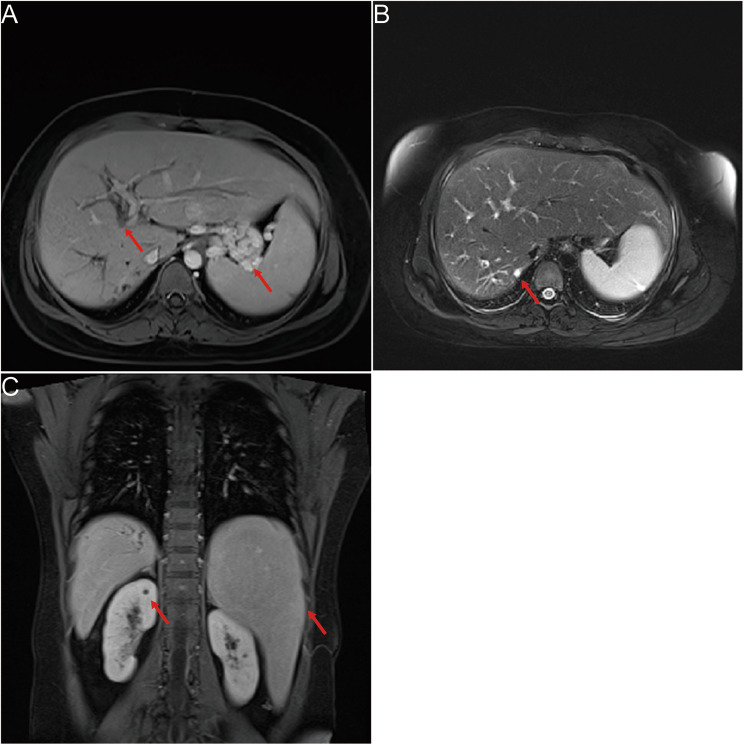

Anti-bacterial therapy (Meropenem injection), anti-inflammatory therapy (Methylprednisolone Sodium Succinate injection), anti-diarrheal therapy (Montmorillonite powder and Loperamide Hydrochloride capsules), and platelet production-promoting therapy (Recombinant Human Thrombopoietin injection) were given. The patient was treated with for Loperamide for 1 day, anti- diarrheal therapy was stopped when symptom improved. After nearly one month of treatment, the levels of WBC, CRP, PCT, CA19-9/125, and liver fibrosis indexes returned to normal, and platelet count increased to 64 × 10^9/L. Biochemical tests revealed normal levels of ALT (16 U/L), AST (19 U/L), TBIL (12.4 µmol/L), DBIL (2.6 µmol/L), TBA (3.4 µmol/L), AKP (40 U/L), and SCr (72 µmol/L). Images revealed dilated intrahepatic bile ducts, full left lobe of liver, full gallbladder, enlarged spleen, and multiple varices in the esophagogastric fundus (Fig. 2 A-C).

Fig. 2.

Imaging findings at discharge and follow-up results of the patient. (A) MRI imaging revealed intrahepatic bile duct dilatation and gastric fundic varices (arrow). (B) MRI imaging revealed cystic dilatation of the intrahepatic bile duct (arrow). (C) MRCP imaging showed the morphological characteristics of bile duct tree